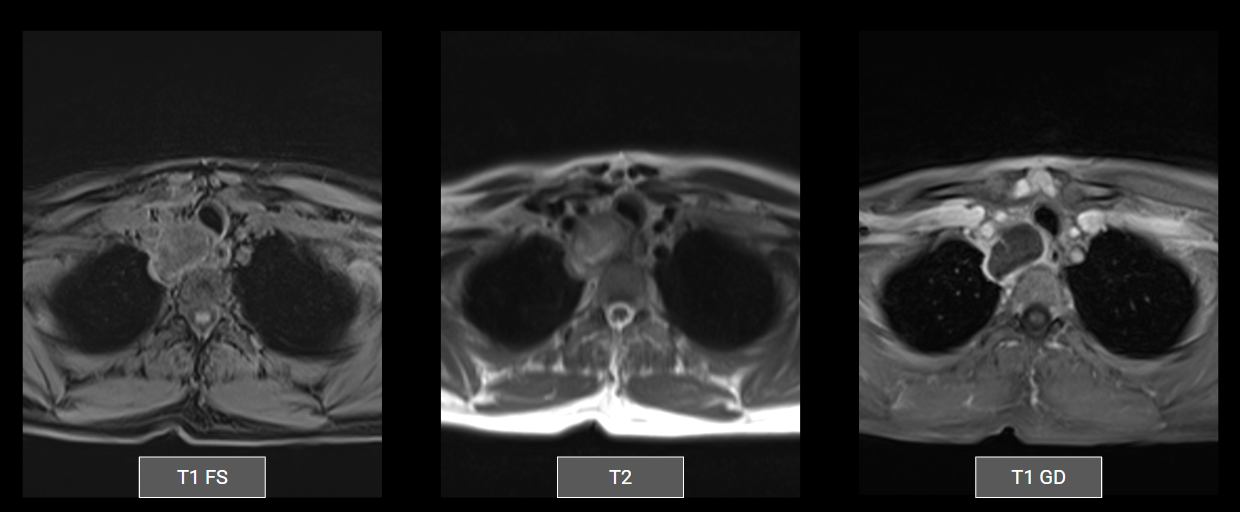

Ressonância do mediastino: